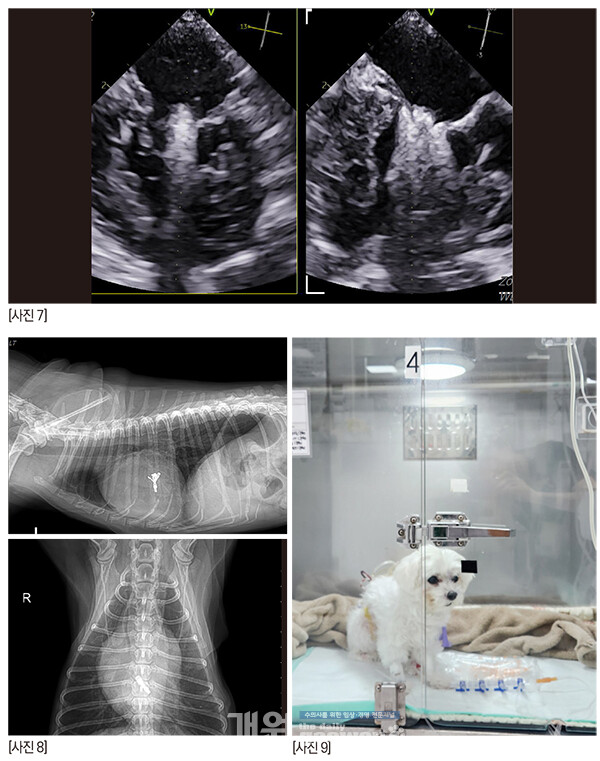

술자가 수술을 타이트하게 준비하고 각오를 하면 아이러니하게도 수술이 별일 없이 흘러간다. 마치 수혈 준비를 하고 수술을 하면 수혈할 일이 안 생긴달까[사진 7].

[사진 8] P1-2 사이의 deep cleft like indentation 때문에 역류는 조금 남겠지만 술 전보다 나은 상황으로 만들고, 거기서 더 이상 진행만 안되면 충분히 괜찮다.매우 매우 걱정했지만 다행히 수술은 무사히 끝났고, 브이클램프를 close하는 시도도 한번으로 끝났다.

수술 2시간 후의 짱아, 정말 대단하다!!!!! [사진 9] 잘 회복해서 3일차에 퇴원을 했지만 나이가 고령이어서 분명 크고 작은 문제들이 수술 2~3주 내에 지나갈 것 같았다.